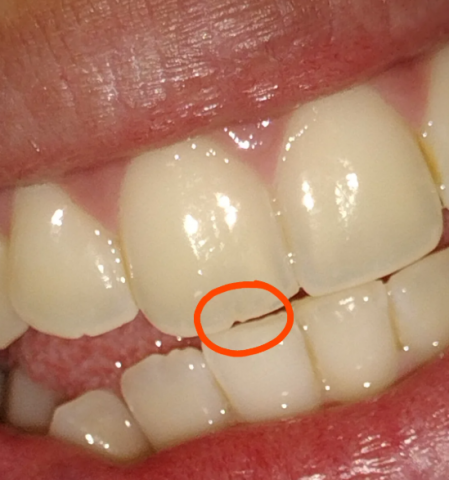

Image Observations: The picture shows the front teeth (incisors). The central incisor (the main front tooth) on the viewer's left has a chipped or fractured corner (incisal angle). A thin, dark, or gray line—the "mini fracture"—appears to run vertically or slightly obliquely from the chipped edge toward the gum line.

Client Statement: "I have chipped front tooth that has mini fracture in it, should I bond it or smooth it out?"

Your concern is whether to choose smoothing (enameloplasty) or bonding (composite restoration). The presence of a "mini fracture" is the critical factor.

Recommendation: Choose Bonding. Smoothing should only be considered if the chip is extremely minor and there is no associated fracture line. Since you see a fracture, bonding is necessary to prevent the fracture from spreading, to protect the nerve, and to achieve the best aesthetic result.